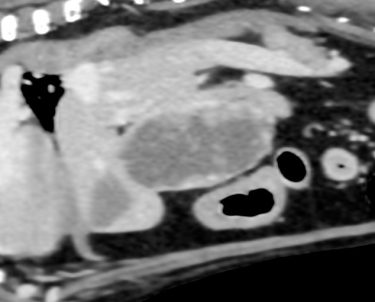

フレンチブルドッグの肝臓に形成されたアポクリン腺癌(転移病巣)☑

症例は定期検査において肝臓に腫瘤性病変が認められた。

1か月ごとの経過観察を行ったが、拡大傾向にあるため、相談して摘出することとなった。

術前検査において、CTを撮影し肝臓の尾状葉に腫瘤が局在することを確認している

腹部正中切開により肝臓腫瘍路露出し、尾状葉を腫瘤と共に切除した。

検索した肝臓では、悪性の上皮性腫瘍が形成されています。以前にアポクリン腺癌の既往歴があり、同様の組織像を呈していることから、その転移性の病変と考えられます。

マージン部に腫瘍性の病変は認められず、腫瘤の摘出状態は良好と考えられますが、進行した転移性の病変が形成されていることから、引き続き、転移の拡大について注意が必要です。